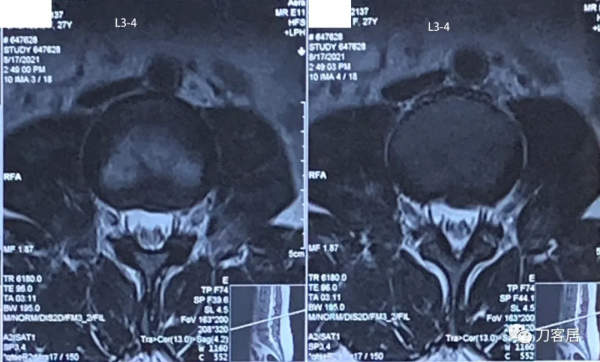

圖5. 20210817術前腰椎MRI橫截面掃描提示L3-4椎間盤輕度突出,左側旁中央型。

該病例有層面MRI顯示腰3-4椎間盤突出,很輕,無需處理。從手術範圍做腰4-5、腰5骶1椎間盤的處理是沒有問題的。